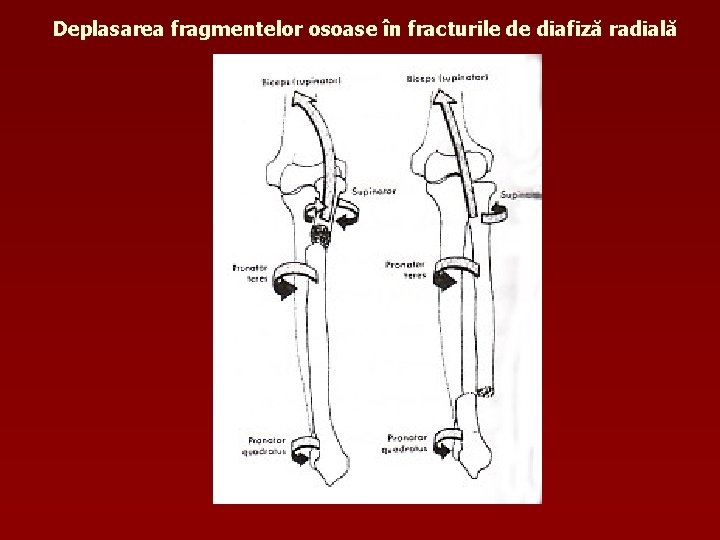

Deplasarea fragmentelor osoase în fracturile de diafiză radială